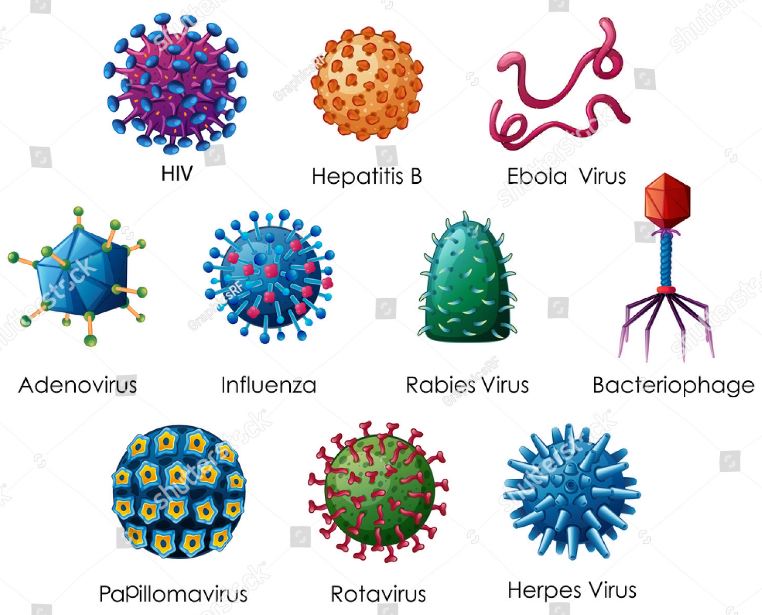

The human body is fashioned in the best possible way and your immune system is one of the best examples of nature’s ways to help you maintain your health. You are constantly threatened by different kind of diseases and infections on a daily basis. Though prevention is better than...

Herpes is one of the most prevalent sexually transmitted infections (STIs) in North America. Many are in search of a remedy to prevent recurrent outbreaks. Currently, one cannot cure herpes. The virus that incites the development of herpes can remain inactive within an individual’s system for a long time....

Genital herpes is often caused by infection of the herpes simplex virus type 2 (HSV-2). Herpes simplex virus type 1 (HSV-1) can also cause genital herpes and more often leads to cold sores, fever blisters. Herpes is not fatal but become dangerous with other virus. There is no specific symptoms...

Chickenpox and shingles Chickenpox and its viral cousin, shingles, are caused by the varicella-zoster virus. They are highly contagious diseases that are more dangerous to teens and adults than to most children. Extreme itchy spots that are raised all over the skin characterize these diseases. Most adults and teens...